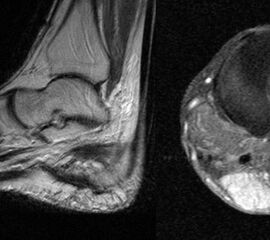

MR-tomographische Darstellung eines unspezifischen weichteiligen Raumforderug im Bereich des dorso-lateralen Rückfußes. Die offene Probebiopsie ergab schließlich die Diagnose eines hochmalignen Synovialsarkoms.

Abbildung 34